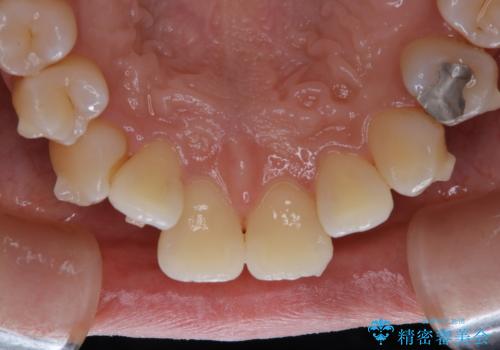

マウスピース矯正インビザライン治療では、歯の表面にアタッチメントという突起を設定します。(アタッチメントは歯の動きを効率的に移動するためのものです)

アタッチメントが歯に付くと、表面が凸凹し磨き残しが多くなったりと、プラークや歯石・着色がつきやすくなることがあります。